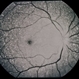

- Wide field fundus photograph of the right eye of the same patient from Liberia demonstrating birefringent crystals in the fovea. Notice the partially fibrosed NVE inferiorly in the macula.